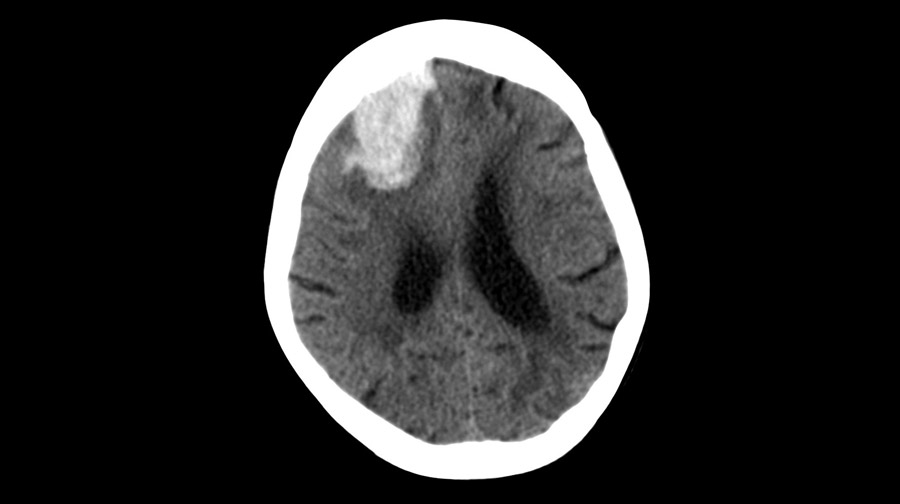

Eliminación temprana mínimamente invasiva de hemorragia intracerebral

En los pacientes en quienes la cirugía se pudo realizar dentro de las 24 horas posteriores a una hemorragia intracerebral aguda, la evacuación mínimamente invasiva del hematoma produjo mejores resultados funcionales a los 180 días que el  tratamiento médico basado en guías. El efecto de la cirugía parece atribuirse a la intervención de las hemorragias lobares. New England Journal of Medicine, 10 de abril de 2024.